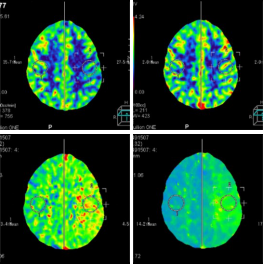

CBT CBV MTT DLY TTP

從圖中CTA可見(jiàn)左側(cè)大腦中動(dòng)脈M 1段閉塞。

腦灌注所示左側(cè)大腦中動(dòng)脈供血區(qū)DLY、 TTP、 MTT時(shí)間顯著延長(zhǎng),CBF略減低, 考慮為 急性腦梗死; 左側(cè)額葉、 頂枕葉CBF、 CBV顯著減低, 符合軟化灶表現(xiàn)。

經(jīng)大動(dòng)脈腦血管造影+機(jī)械血栓清除+動(dòng)脈內(nèi)溶栓術(shù), 顯示血管病變位置與CTA顯示病變 位置相符, 治療后, 該血管供血區(qū)域得到明顯改善。

核磁共振檢查證實(shí)梗死核心區(qū)域與灌注圖所示區(qū)域匹配。

患者術(shù)后復(fù)查腦血管灌注一站式檢查, 腦血管CTA顯示原閉塞的左側(cè)大 腦 中 動(dòng) 脈M 1段 此 次 顯 影 通 暢 , 局 部 中 度 狹 窄 。 腦 灌 注 分 析 顯 示 左 側(cè) 額 葉 及 頂 枕 葉 軟 化 灶 改 變 , 基 本 同 前 ; 原 左 側(cè) 的 大 腦 中 動(dòng) 脈 供 血 區(qū) 大 面 積 灌 注 異 常 較 前 明 顯 改 善 。2 0 1 8 - 1和 2018 - 5月兩次復(fù)查, 都顯示原堵塞血管通暢, 與溶栓后對(duì)比無(wú)明顯變化。

640層寬體探測(cè)器CT為16 cm覆蓋不動(dòng)床一站式神經(jīng)成像, 通過(guò)一次注藥, 一次掃描可以 獲得完整的純動(dòng)脈期、 純靜脈期和腦血流功能灌注成像及動(dòng)態(tài)CT- DSA電影圖像, 每一個(gè)動(dòng) 態(tài) 數(shù) 據(jù) 都 是 在 同 一 時(shí) 相 獲 得 , 同 時(shí) 包 含 了 解 剖 和 功 能 的 信 息 , 通 過(guò) 對(duì) 神 經(jīng) 一 站 式 的 快 速 分 析, 在60 秒內(nèi)就可以完成急性腦卒中的全面評(píng)估。

不動(dòng)床的采集模式避免了螺旋穿梭式灌注帶來(lái)的全器官不在同一時(shí)相采集、 連續(xù)曝光劑 量大的不足; 獨(dú)有的SVD+算法帶來(lái)精準(zhǔn)的灌注結(jié)果, 結(jié)合獨(dú)有的全顱冠狀位和矢狀位的灌 注圖及血管與灌注融合圖像可以清楚顯示梗塞血管及其造成的低灌注區(qū)域, 帶來(lái)精準(zhǔn)的檢查 結(jié)果。

此外, 機(jī)器同時(shí)搭載了雙空間多模型的AIDR 3 D迭代技術(shù), 使得神經(jīng)一站式檢查的劑量 僅需2 - 3 m Sv,造影劑用量?jī)H需40 ml,有效降低了檢查所需的輻射劑量和造影劑用量, 特別 適合需要多次復(fù)查的患者。